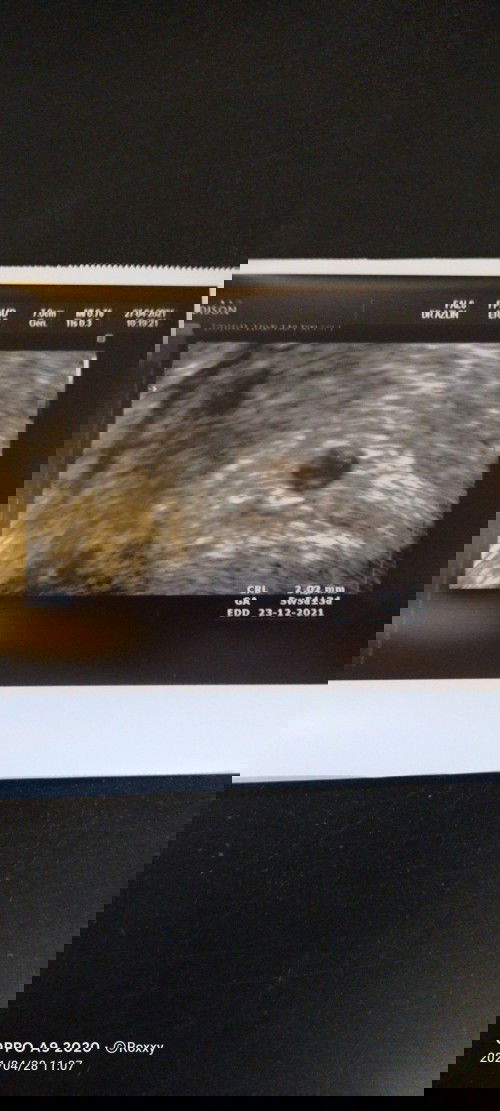

Assalam ibu bapa sekalian. Saya seorang yg menjalani rawatan IVF. Semalam saya saya buat follow up check up. Result yg diterima mengecewakan serta sedih sebagai seorang yg menanti zuriat sekian lama. Saya #ingintahu, sekiranya gagal dalam menjalani rawatan IVF tersebut. Adakah saya perlu menjalani pantang seperti orang bersalin? Mohon kongsi jawapan dari sesiapa yang boleh membantu saya. Terima kasih.